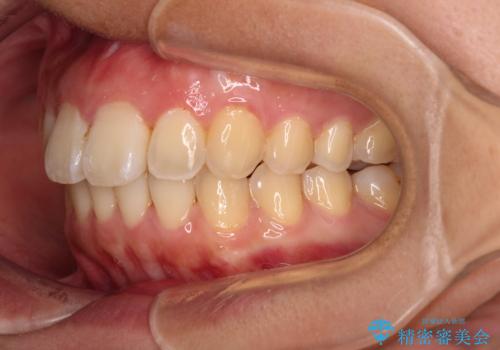

- 前方に傾斜した上下の前歯を気にして来院された患者様です。

唇の閉じにくさや横顔のシルエットが気になるような突出感ではなかったため、インビザラインを用いて、歯列の遠心移動とIPR(歯と歯の間を削る)により前歯の傾斜を改善していくこととしました。

スムーズに終了すると思われましたが、インビザライン矯正独特の奥歯が咬み合わない状態が続き、更には遠方へ転居されたこともあり、治療期間は長引いてしまいました。